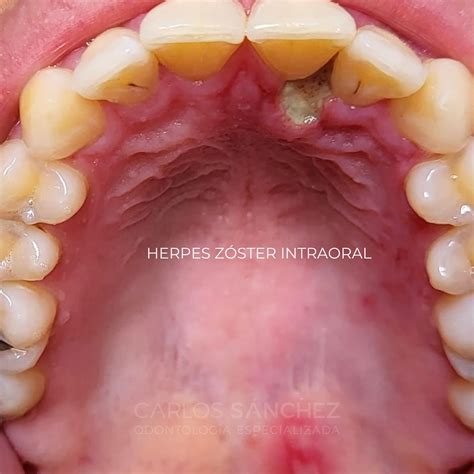

Como el VHS, el VVZ persiste en los ganglios sensitivos. La existencia de una inmunidad celular disminuida favorece su reactivación y la aparición de un herpes zóster en el dermatoma inervado por el ganglio sensitivo correspondiente. Este es el motivo por el que el herpes zóster se presenta sobre todo en pacientes de edad avanzada y con una inmunidad disminuida. Antes de la erupción de las lesiones cutáneas, el paciente presenta de forma característica neuralgias segmentarias y prurito. En la piel aparece un exantema vesicular, limitado al dermatoma afectado, sobre un fondo eritematoso que evoluciona primero a pústulas y finalmente a costras. La afectación de la segunda y de la tercera ramas del trigémino puede dar lugar a alteraciones de la mucosa oral. Las vesículas intraorales estallan rápidamente y confluyen, lo que da lugar a erosiones. Las localizaciones más habituales son la mucosa de los labios, de la lengua, del paladar blando y del paladar duro así como la mucosa yugal, si bien las lesiones intraorales suelen ser estrictamente unilaterales.

Figura 3. Herpes zóster de la mucosa oral con afectación de la rama II del trigémino en el lado izquierdo.

Después de la cicatrización de las vesículas en un plazo de 2-3 semanas puede persistir un dolor intenso que se denomina neuralgia postherpética. En algunas ocasiones, este dolor puede simular una pulpitis. Antes de la aparición de las vesículas debe hacerse el diagnóstico diferencial con una neuralgia. El diagnóstico puede ser clínico o establecerse, como en la infección por el VHS, mediante el test de Tzanck, la inmunofluorescencia directa, la hibridación in situ, la PCR o un cultivo vírico. El herpes zóster se trata con antivirales sistémicos en pacientes mayores de 50 años, en caso de neuralgias intensas antes de la erupción cutánea o en cuanto aparece ésta, en el herpes oftálmico y en pacientes inmunodeprimidos. Las lesiones orales dolorosas se tratan con colutorios con efecto anestésico local y analgésicos sistémicos.